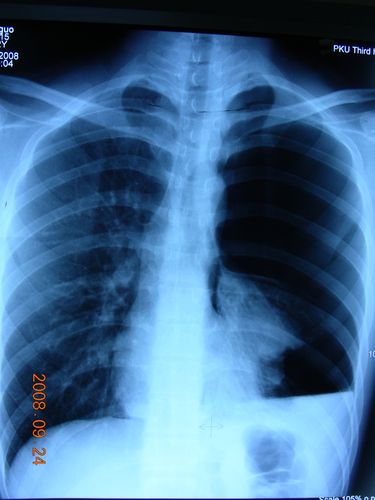

气胸的x线表现

气胸的x线表现图片